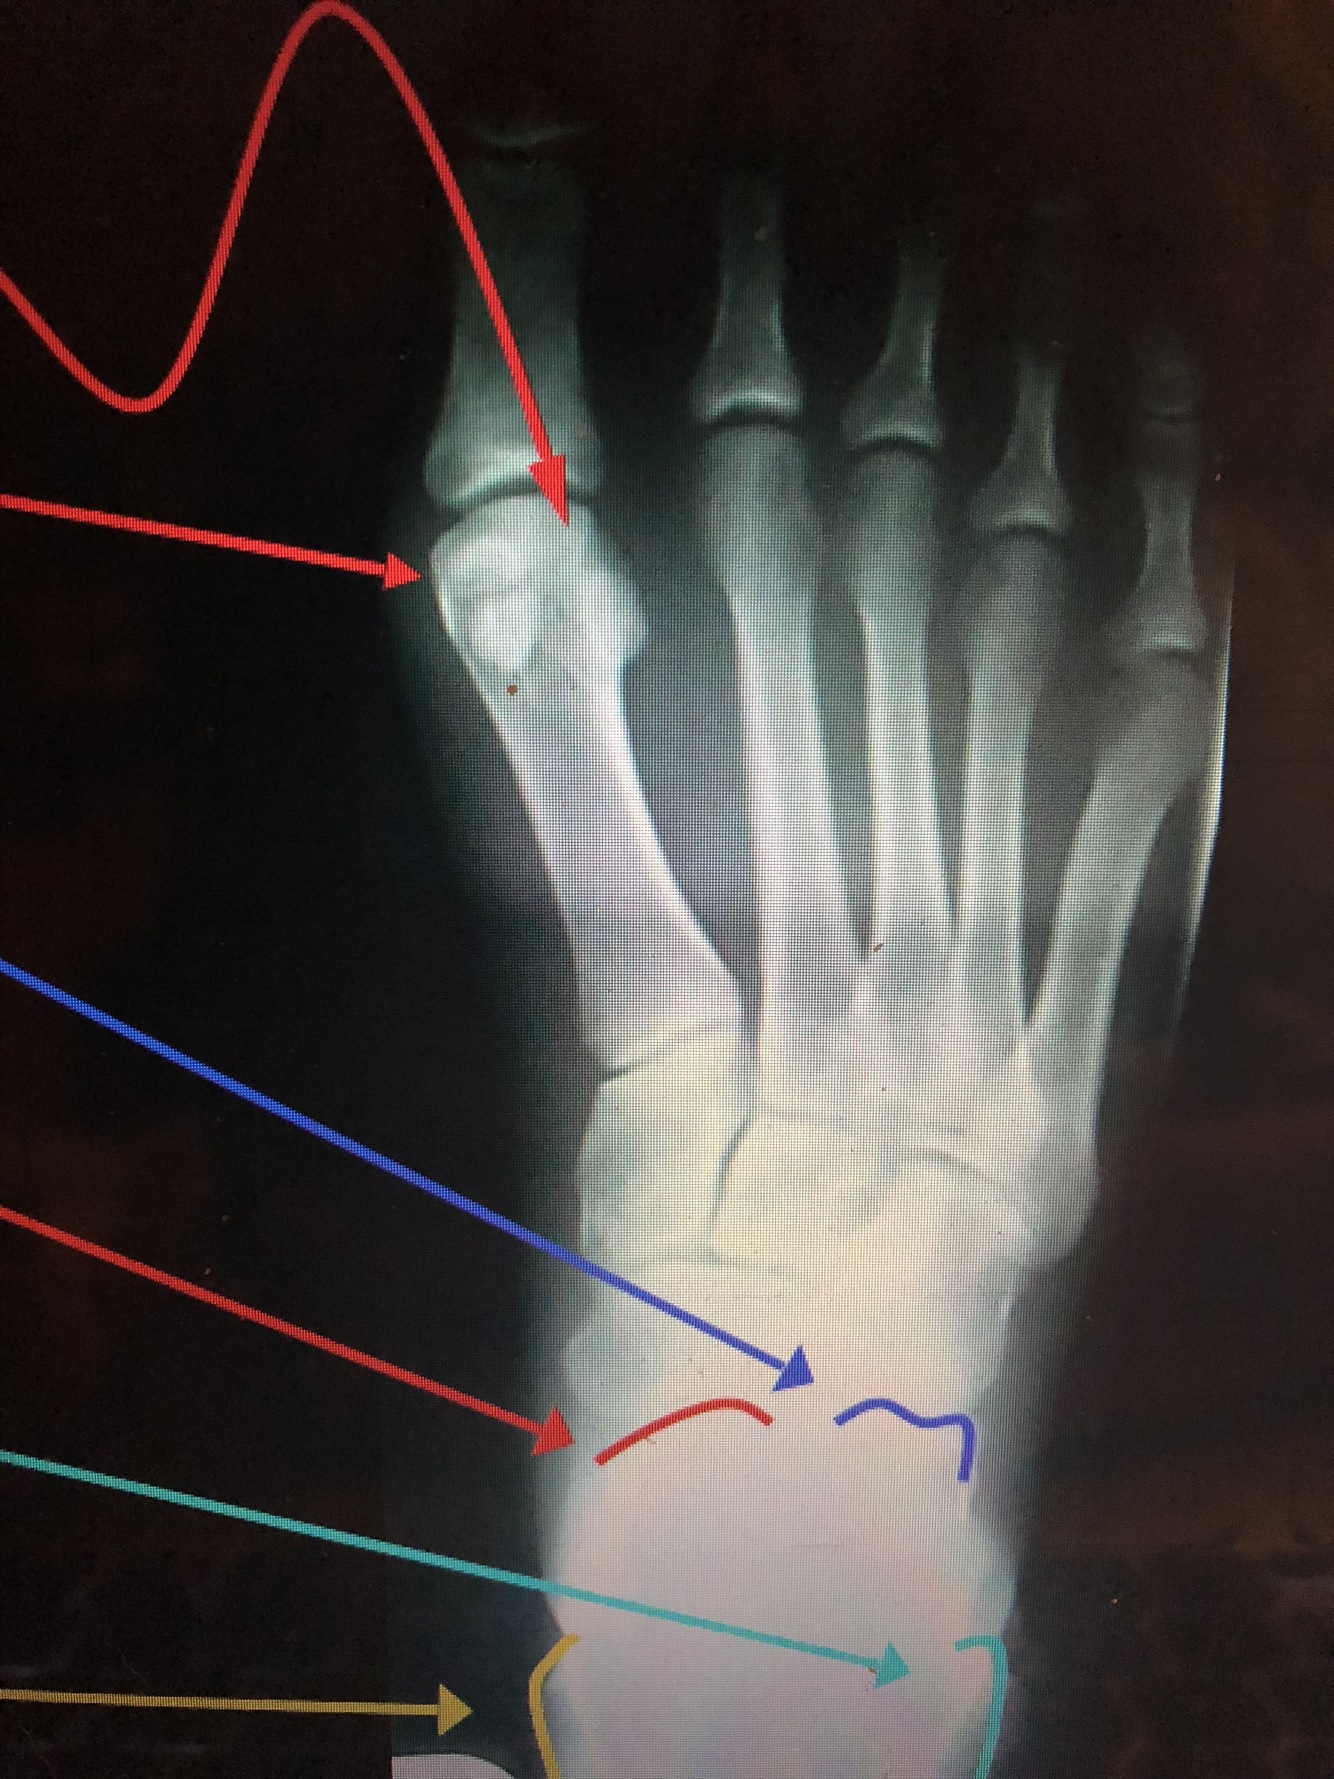

What are the top two red lines?

Sesamoid Bones

•Found in the tendon of the flexor hallucis brevis

What bone is dark blue?

Calcaneus

What bone is the bottom red line?

Talus

What is the light blue lines?

Lateral Malleolus

What is the yellow line?

Medial Malleolus

What is the red line?

head of 1st metatarsal

What is the dark blue line?

Neck of 2nd metatarsal

Shaft of 3rd metatarsal

What is the light blue line?

base of the 3rd metatarsal

Styloid Process of the 5th Metatarsal

• Common fracture site in an inversion ankle sprain due to the pull of the peroneus brevis muscle